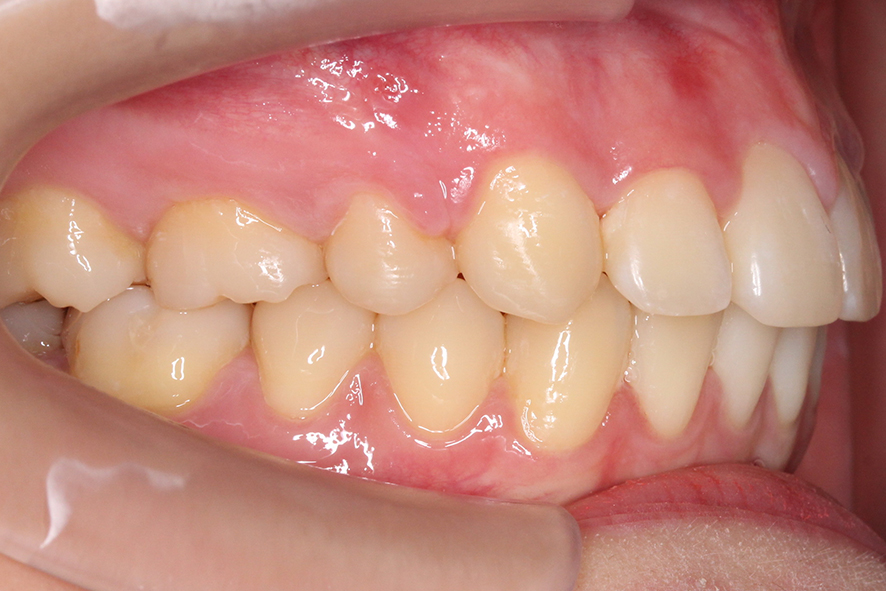

돌출입 교정 후 overbite 사진을 보면

하악이 거의 보이지 않게 깊게 물리던

deep bite 증상이 사라진 것을 확인할 수 있는데요,

전치부 교합 시 벌어진 부분 없이

상하악 치아가 잘 맞닿는 모습입니다.

돌출이 심했던 측면의 overjet 모습 또한

교정 후 상악의 돌출감이 사라진 모습으로

중절치가 뻐드러지는 증상이 사라진 모습입니다.

좌우의 교합평면을 확인해보면 어금니 부분의

상하악 교합 상태가 정상적인 교합 상태로

돌아온 모습인데요, 어금니가

교합되는 위치도 바르게 바뀌었고

상악의 돌출 증상도 사라졌습니다.